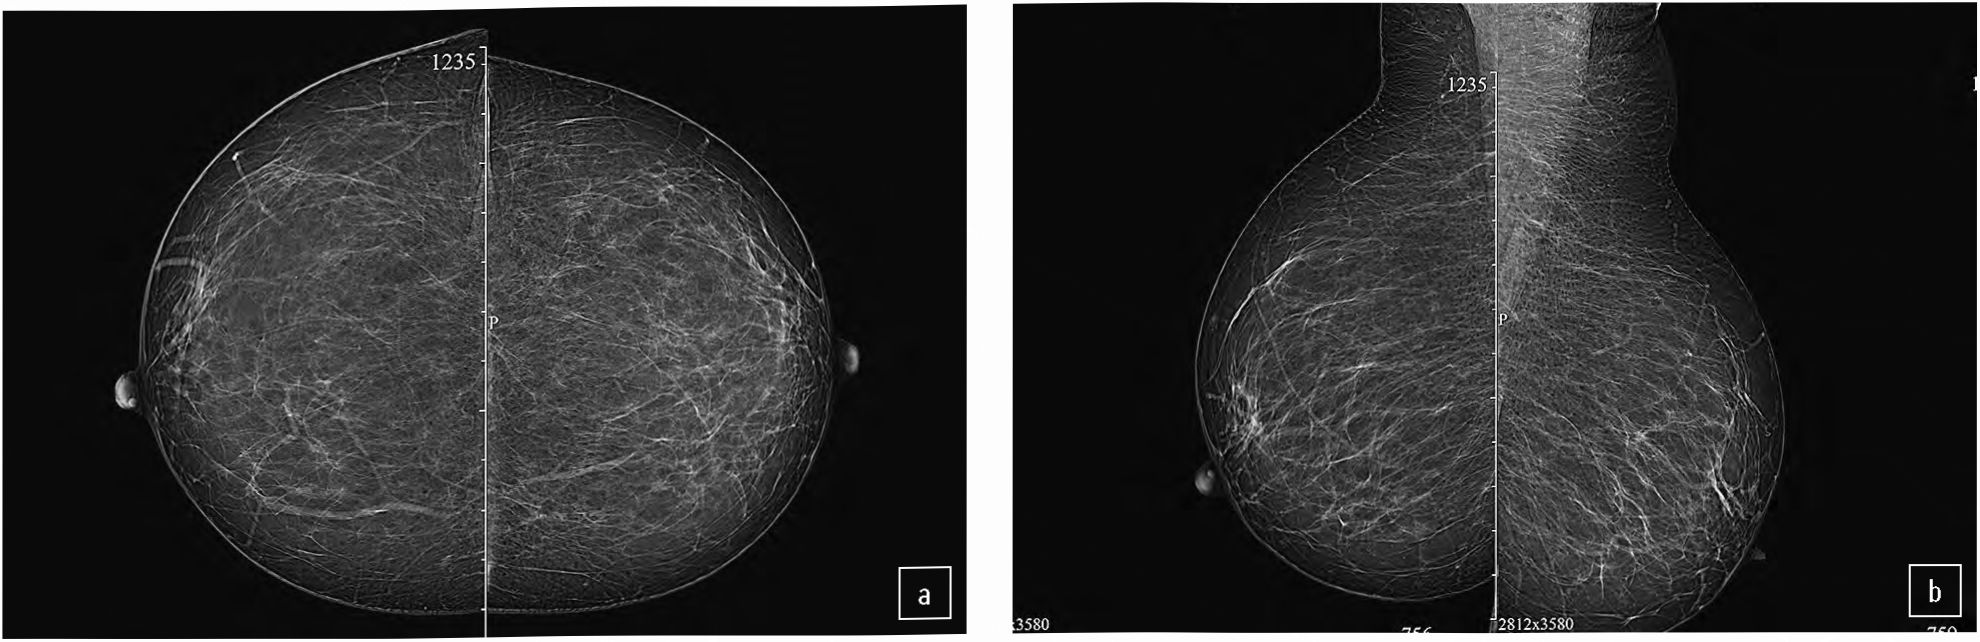

Выполнена маммография. Плотность молочной железы – тип А по Ас R. На фоне фиброзно-жировой инволюции узловые образования и скопления микрокальцинатов не дифференцируются. Аксиллярная область с обеих сторон без патологии. BI-RADS 1 (рис. 1).

Рис. 1. Больная С., 82 года, маммография: а – краниокаудальная проекция; b – медиолатеральная проекция. Кожа молочных желез не утолщена, сосок не втянут. Плотность молочной железы тип А по АСR. На фоне фиброзно-жировой инволюции узловые образования не дифференцируются. BI-RADS 1.

Fig. 1. Patient S., 82 y.o., mammography: a – craniocaudal view; b – mediolateral view. The skin of the mammary glands is not thickened, and the nipple is not retracted. Type A breast density according to ACR. Fibrous-fatty involution with no nodular masses was observed. BI-RADS 1.